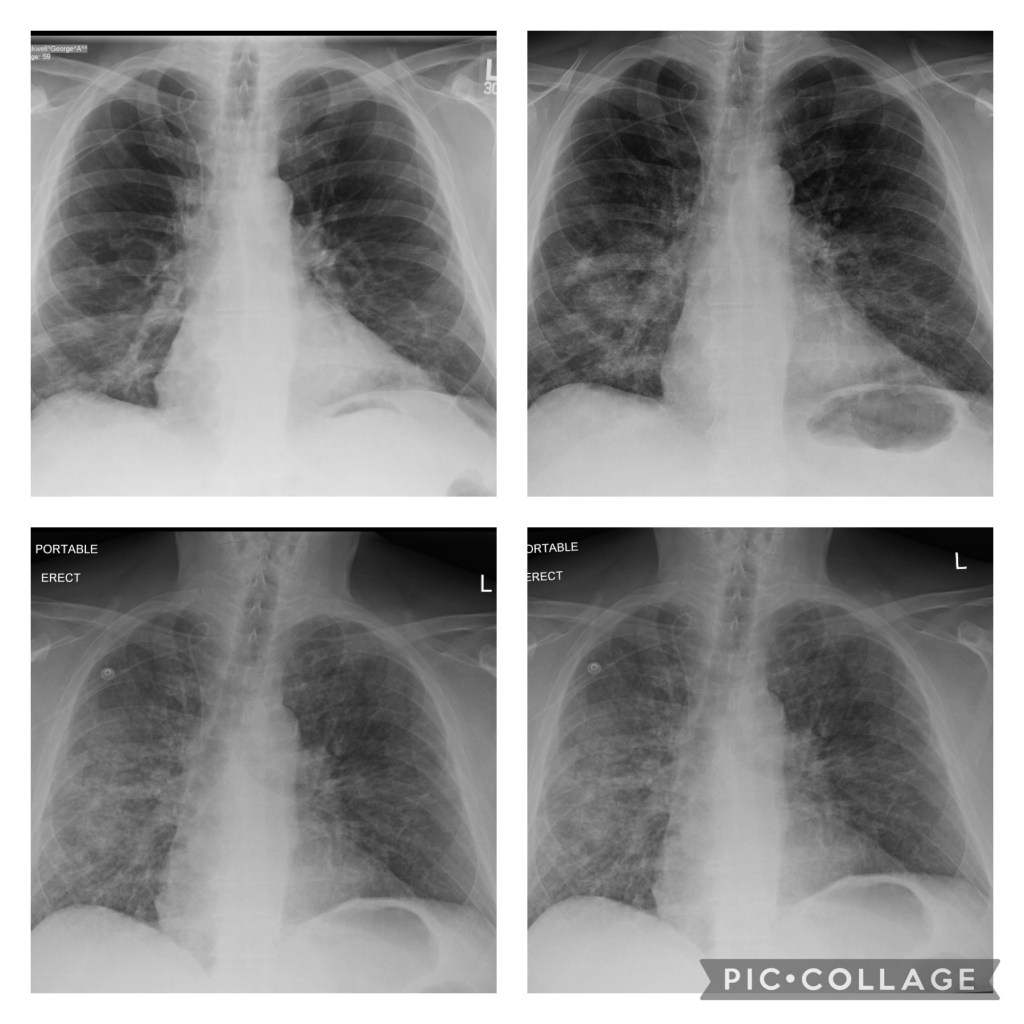

The doctors had him hooked up to three different antibiotics and he was given some heavy duty cough syrup, but he didn’t seem to be improving. He was sent down for chest X-rays pretty regularly and they showed his lungs were actually getting worse and his cough was still as persistent as ever. This concerned the pulmonology team. They now suspect he has Pneumocystis pneumonia. It is a fungal pneumonia, rather than a bacterial one, which would explain why the antibiotics aren’t doing anything.

Pneumocystis pneumonia (PCP) is a serious infection caused by the fungus Pneumocystis jirovecii. Most people who get PCP have weakened immune systems, meaning that their bodies don’t fight infections well. About 30-40% of people who get PCP have HIV/AIDS. The other people who get PCP are usually taking medicine that lowers the body’s ability to fight germs or sickness or have other medical conditions, such as:

Because George has been undergoing chemotherapy which greatly lowers his blood counts and thereby his immune system, he is vulnerable to this infection.

She explained the treatment for PCP – basically steroids and an anti-fungal called Bactrim. He was started on that yesterday. I asked her how effective this treatment is on people with severely compromised immune systems, like George and she said she was “hopeful.” Not the most encouraging response I could have heard….She said that it’s a serious infection and that people do die from it.